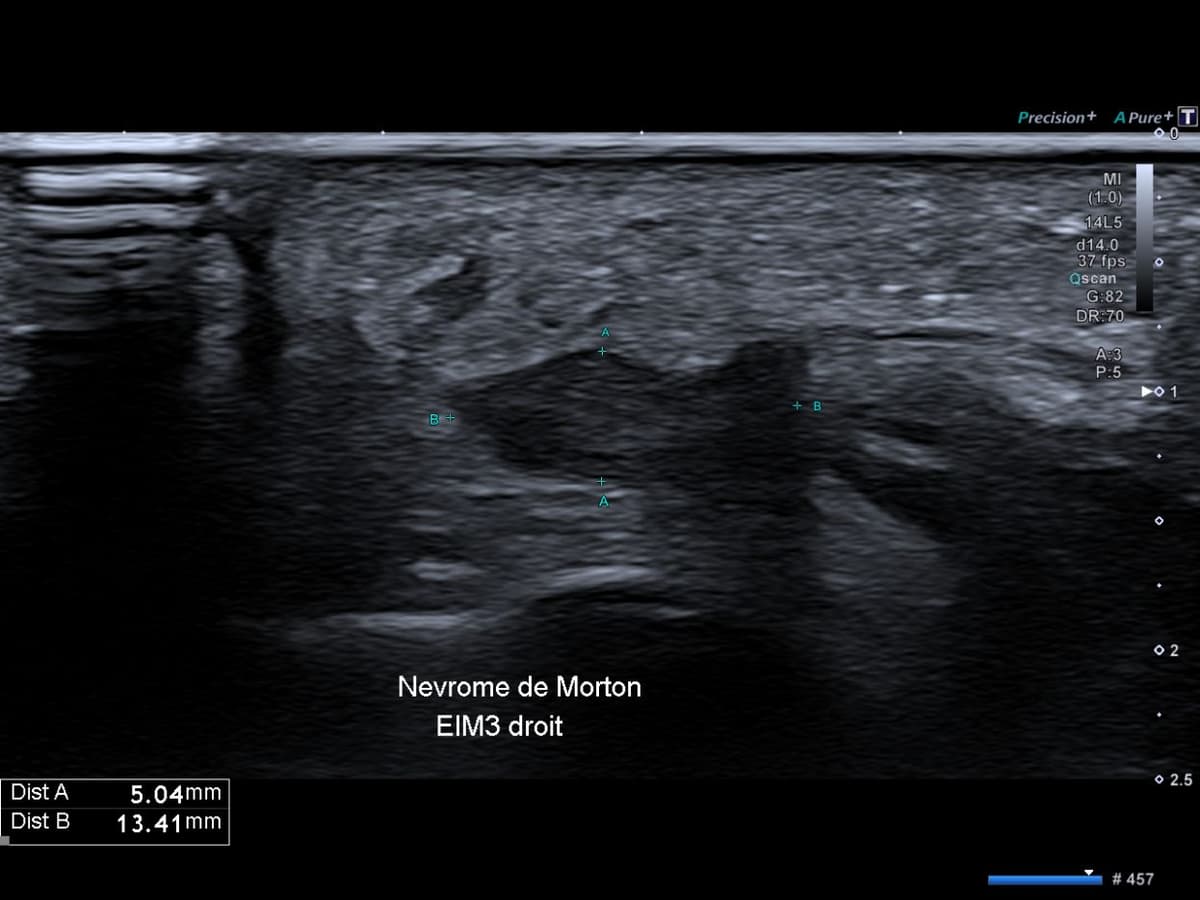

Nevrome de Morton

Métatarsalgie centrale non traumatique chronique du 3ème espace inter métatarsien.

US